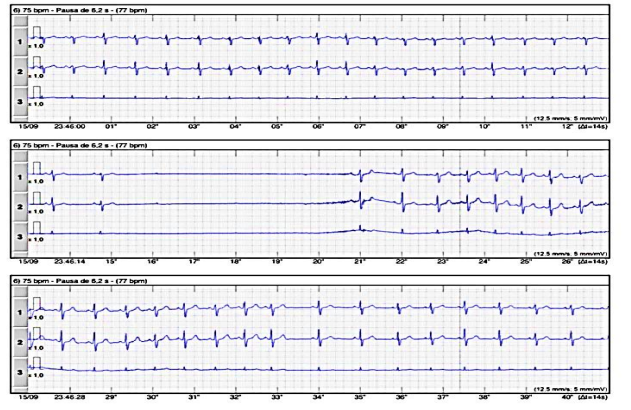

Observe o traçado do ECG a seguir.

A imagem apresentada sugere

Paciente obeso, sem cardiopatia estrutural, 38 anos, numa avaliação de rotina, cujo Holter 24 horas apresentou no exame o traçado representado na imagem abaixo.

Diante dos dados apresentados nesse caso, a hipótese diagnóstica é de